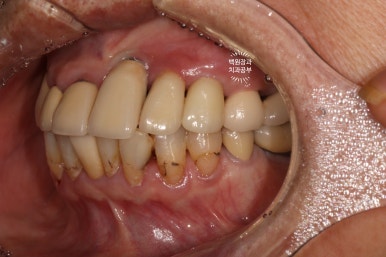

처음 오셨을 때 정면 사진입니다.

잘 보시면, 아까 보였던 치과용 파노라마 사진대로 뿌리만 남은 두 개의 치아를 찾아보실 수 있으실거에요. ㅎㅎ

제가 서두에서 어금니에 스트라우만 임플란트가 많다고 말씀드렸는데, (나머지도 branemark 제품으로 보이며, 명품으로 주름잡던 스웨덴 임플란트 입니다.) 이 미친 퍼포먼스의 스위스 임플란트는 20년이 지난 지금도 짱짱한 성능을 자랑하고 있답니다.

아까 말씀드렸듯, 왼쪽 위 송곳니와 오른쪽 아래 작은어금니에 뿌리만 있는 잔존치근이 관찰됩니다.